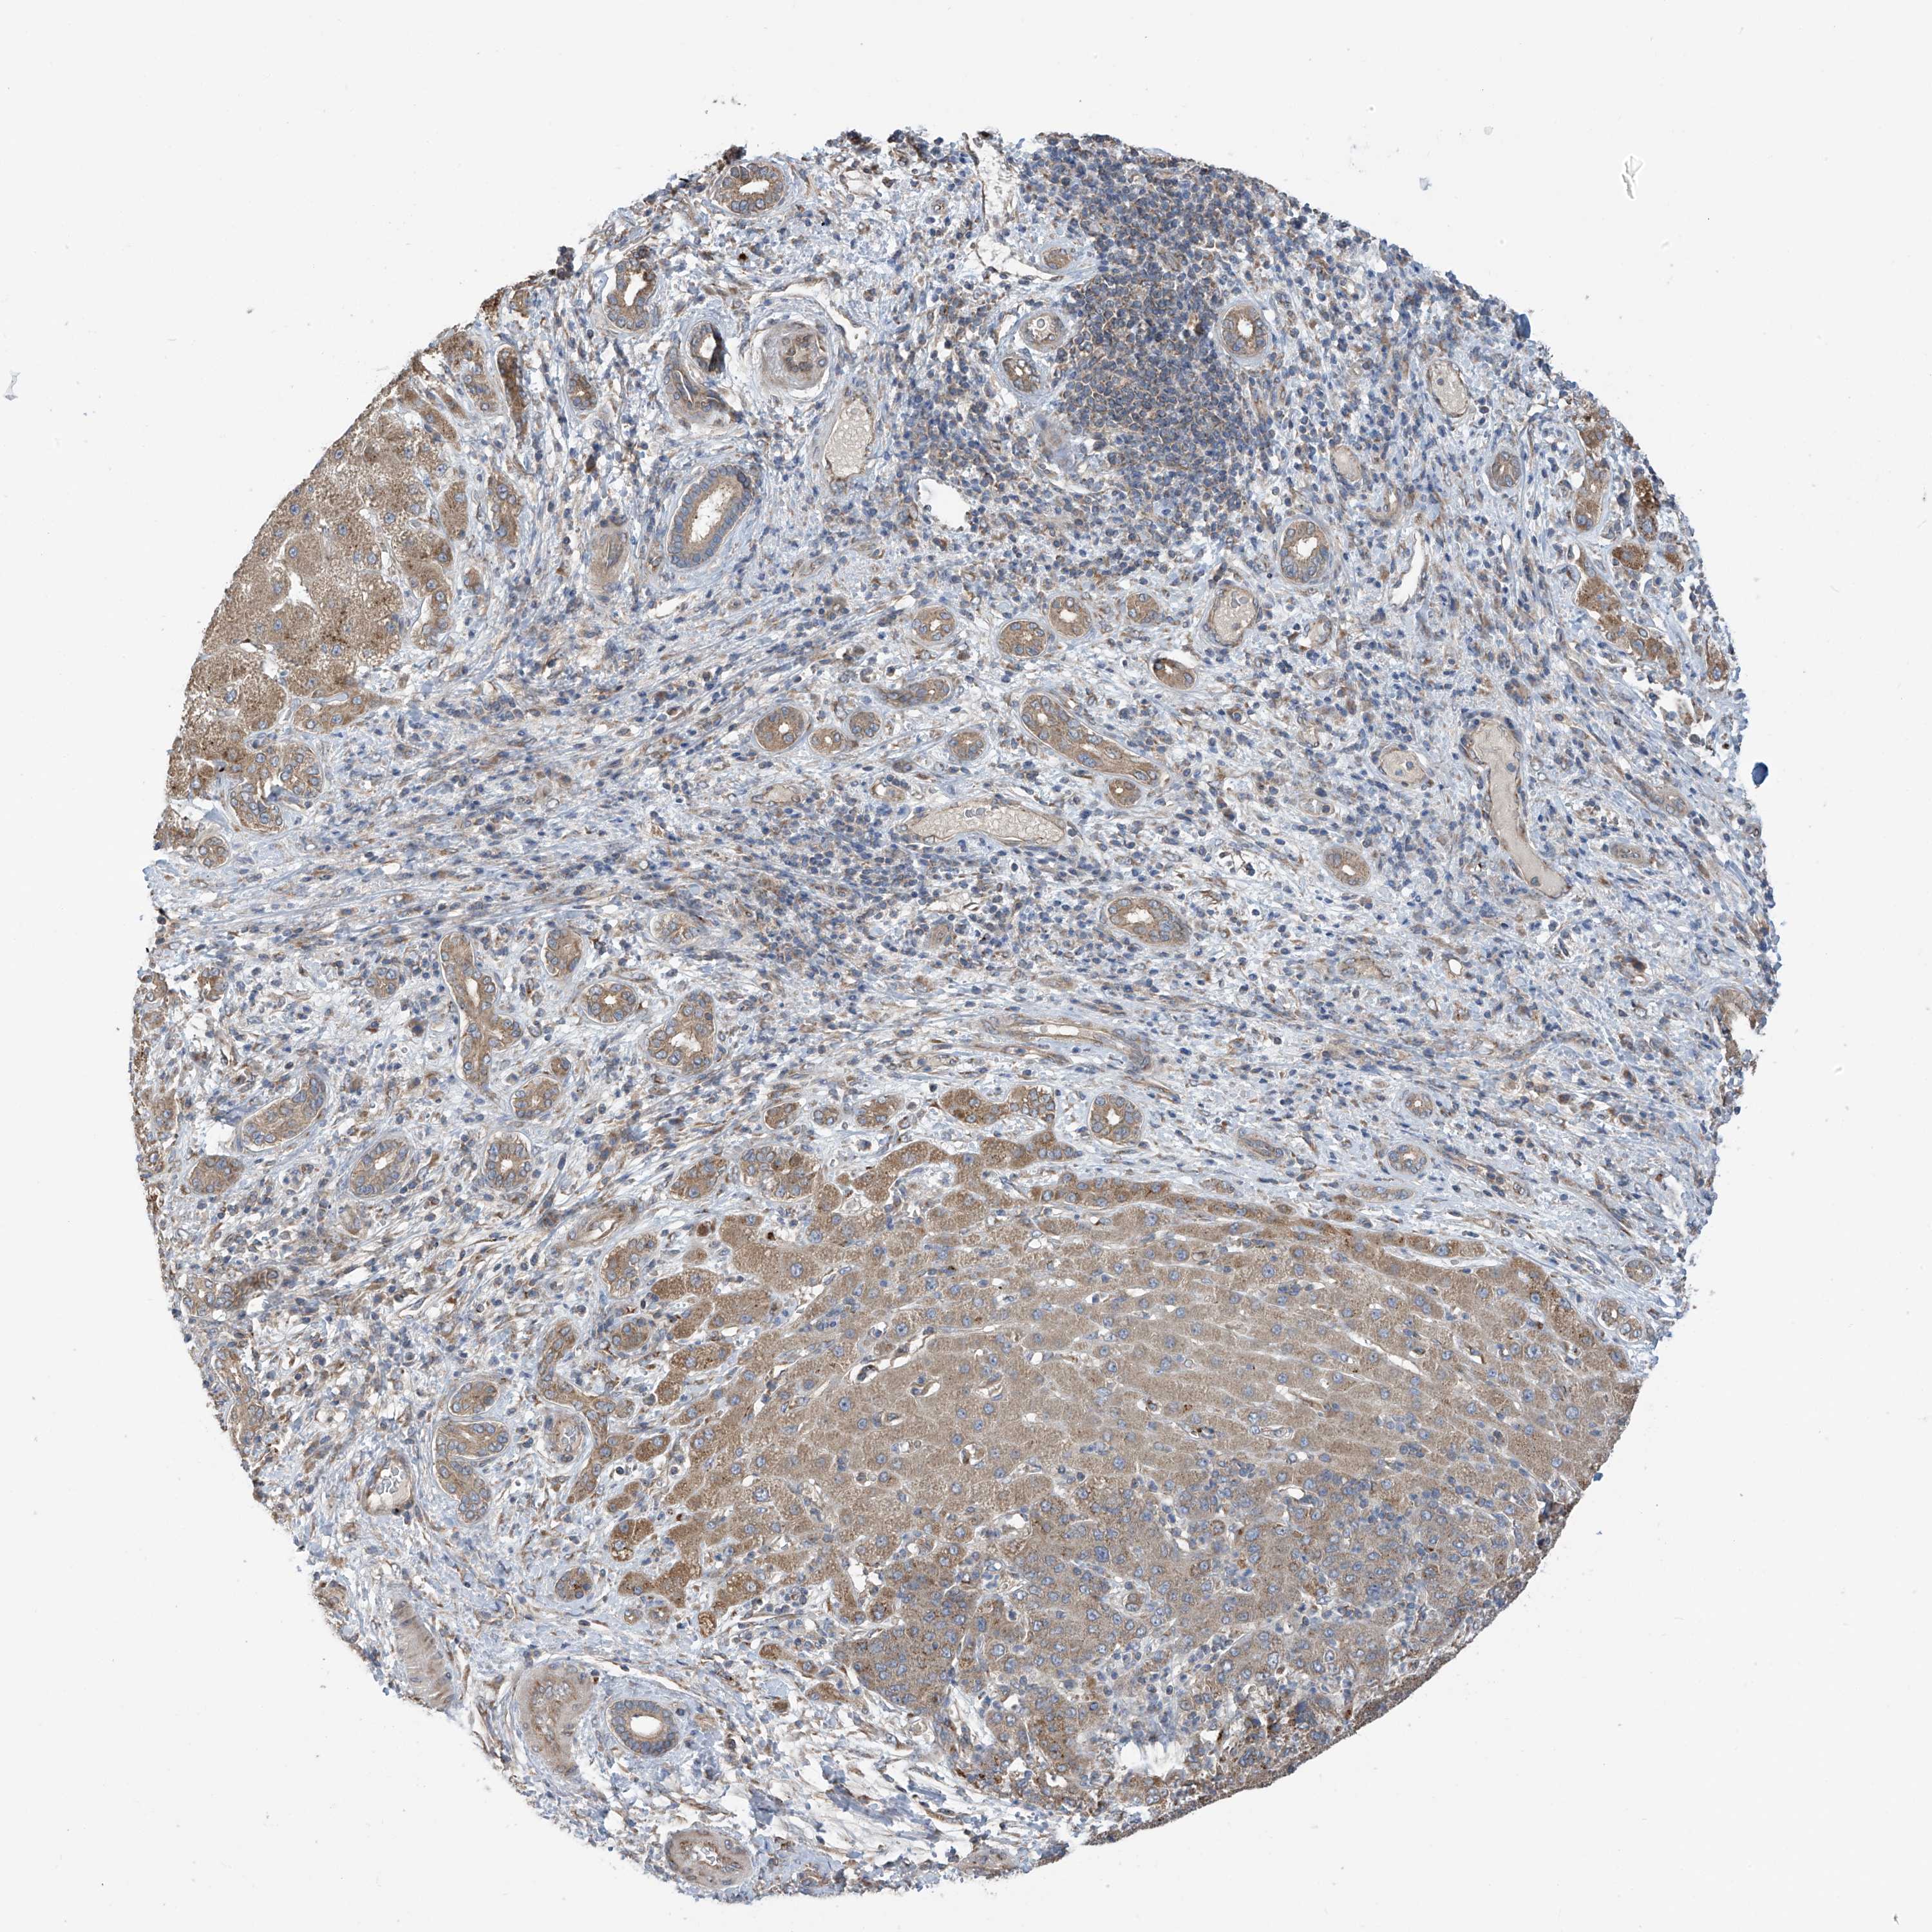

LIVER CANCER - Protein expressioni

A mouse-over function shows sample information and annotation data. Click on an image to view it in a full screen mode. Samples can be filtered based on level of antibody staining by selecting one or several of the following categories: high, medium, low and not detected. The assay and annotation is described here.

Note that samples used for immunohistochemistry by the Human Protein Atlas do not correspond to samples in the TCGA dataset.

Antibody stainingi

Antibody staining in the annotated cell types in the current human tissue is reported as not detected, low, medium, or high, based on conventional immunohistochemistry profiling in selected tissues. This score is based on the combination of the staining intensity and fraction of stained cells.

Each image is clickable and will lead to virtual microscopy that enables deeper exploration of all samples and also displays staining intensity scores, fraction scores and subcellular localization as well as patient and tissue information for each sample.

Antibody HPA034602

Antibody HPA034603

Antibody CAB033424

Staining

High

Medium

Low

Not detected

Intensity

Strong

Moderate

Weak

Negative

Quantity

>75%

75%-25%

<25%

None

Location

Nuclear

Cytoplasmic/membranous

Cytoplasmic/membranous,nuclear

Cholangiocarcinoma

Carcinoma, Hepatocellular, NOS